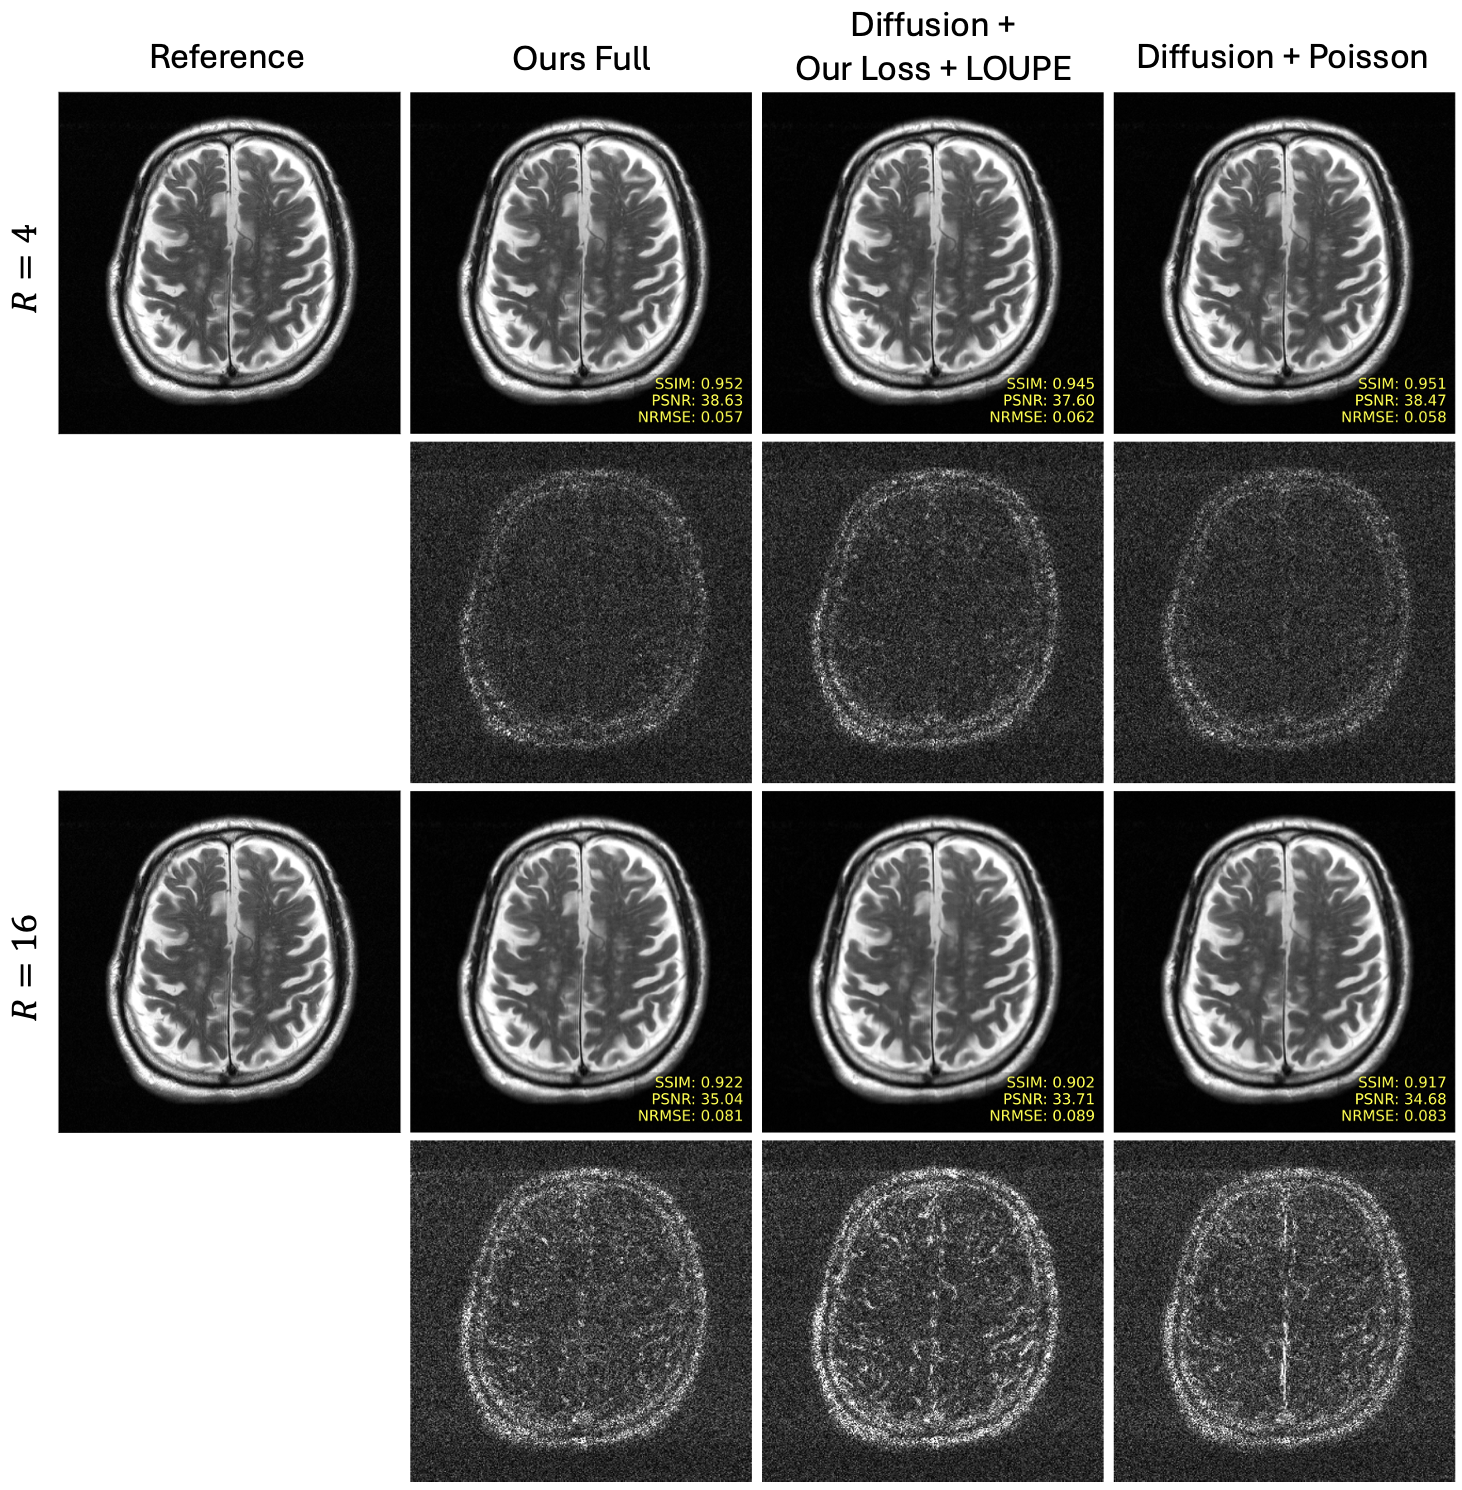

Fig. 3 presents slices reconstructed from k-space data under-sampled by with diffusion-models using a Poisson mask and masks optimized with our loss + LOUPE and our full method for PDFS knee, T2 brain, and PD knee data. Our full method achieves improved quantitative metrics, and the zoomed-in areas indicate that our proposed reconstruction produces slices with more fine structural details than those reconstructed with the other diffusion model-based methods. Similarly Fig. 4 and Fig. 5 show reconstructed slices, along with error maps, at and for T2 brain and PD knee data respectively. Again, our method, with its optimized sampling pattern, achieves improved quantitative and qualitative performance in comparison to the competing diffusion-based methods.

Fig. 6 presents quantitative comparisons of peak signal-to-noise ratio (PSNR), structural similarity index measure (SSIM) [50] and normalized-root-mean-square-error (NRMSE) of reconstructed slices with acceleration factors of . Our full method outperforms the other two diffusion-based methods across all anatomies, metrics, and accelerations, suggesting that our approach for learning sampling patterns may be better suited for diffusion-based reconstructions in comparison to Poisson Disc patterns and multi-coil LOUPE. Quantative MoDL results are also presented for reference. Since MoDL optimizes an NRMSE objective end-to-end during training, it generally achieves similar or lower NRMSE and PSNR in comparison to the diffusion-based methods. However, the proposed diffusion-based method achieves better SSIM than the end-to-end methods in all settings but PD knee data, where the two methods perform comparably.